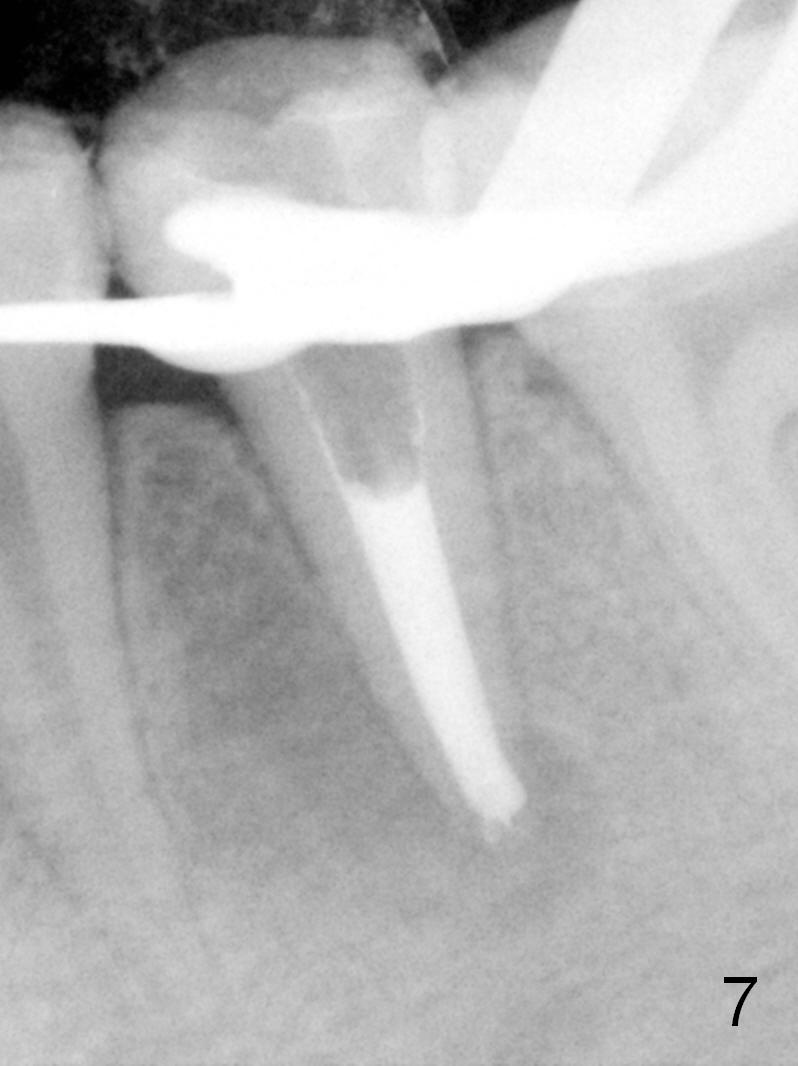

A 13-year-old girl has a buccal apical fistula at the tooth #20 with large periradicular radiolucency (Fig.1 *). After canal debridement, calcium hydroxide paste is placed in the canal (Fig.2 *). One month later, the fistula does not disappear with light percussion. New paste is placed (Fig.3). Two months later, the fistula disappears without percussion. The existing paste (Fig.4) is changed (Fig.5 (yellow: radiolucency; red: Inferior Alveolar Canal)). Another 2 months later, the fistula does not recur; as before, the paste density decreases, so does periradicular radiolucency (Fig.6). Root canal is packed (Fig.7). Six months postop, periradicular radiolucency continues to decrease, while the lamina dura at the apex is discontinuous (Fig.8 between arrowheads). Seven years postop, the lamina dura at the apex is seemingly intact (Fig.9). The patient remains asymptomatic at #20. In fact there is an acute infection at #29.